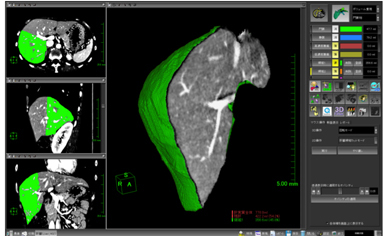

肝臓には動脈,門脈,静脈などの血管系が存在し,複雑に走行しています。その内部の血管走行をあらかじめ知っておくことは,肝切除術の術前情報として非常に重要です。肝臓解析ソフトウェアでは,新しいレンダリング技術を採り入れることにより,肝臓内部の血管走行を明瞭に表現することを可能にしました(図5)。さらに,血管支配領域をシミュレートした際の境界面にMPRを表示させることも可能です(図6)。それぞれの血管の位置関係や距離,腫瘍付近の血管の詳細情報,および対象物の肝臓表面からの位置関係などを明瞭に表現することができます。

![]() 図6 肝臓解析ソフトウェア カット面にMPRを表示させることで,組織に対する血管走行を明確に表示できます。 |